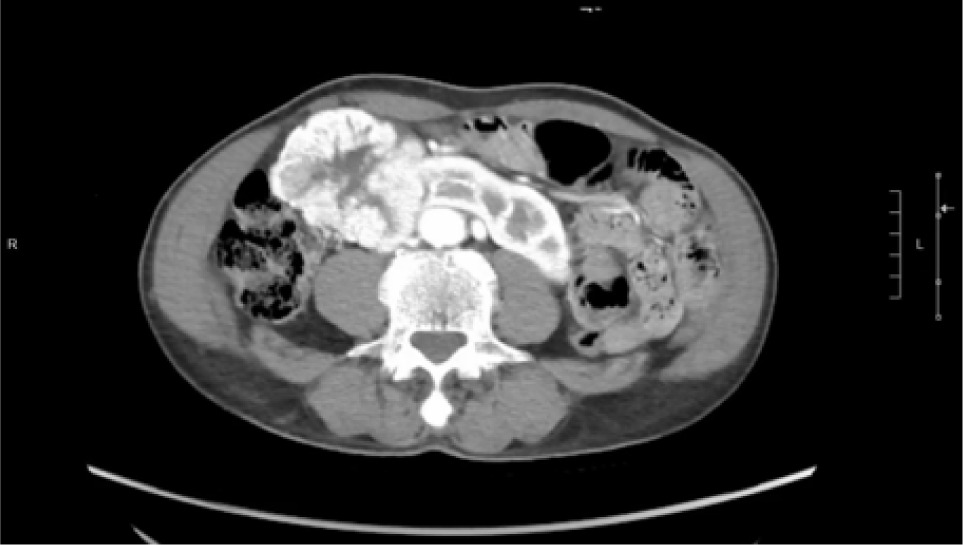

A 74-year-old Chinese male patient, ex-smoker, and social drinker, with a history of carcinoma of prostate in remission with laparoscopic radical prostatectomy done 11 years ago presented with an incidental finding of a right abdominal mass without frank symptoms. Preoperative eGFR ranges from 80 to 90 mL/min/1.73m2. Computed tomography (CT) showed a 7 cm heterogeneous mass on the right side of the HSK with complex hilar anatomy (Figures 1 & 2). Dual tracer (C-11 acetate and F18 FDG) positron emission tomography (PET-CT) showed moderate and mildly avid renal cell carcinoma (RCC) arising from HSK, without nodal or distant metastases. A 3D image reconstruction using FUJIFILM Synapse system was performed, showing complex tumor and vascular anatomy (two renal arteries and an additional artery to isthmus) (Figure 3). An open partial right nephrectomy was planned.

Figure 1: Axial cut of arterial phase-enhanced CT abdomen at the tumor level.

Figure 2: Axial cut of delayed phase-enhanced CT abdomen at the tumor level.